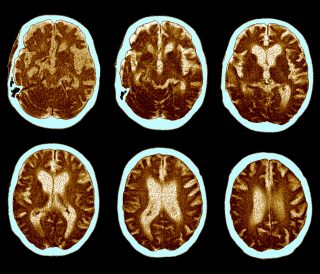

The purpose of the drug is to clear harmful accumulations of a protein called beta-amyloid from the brain. This naturally occurring protein appears to be abnormally high in the brains of Alzheimer’s patients. It clumps together to form plaques that collect between neurons and disrupt cell function. This, in turn, leads to cell death.

Initially, Alzheimer’s disease tends to destroy neurons and their connections in parts of the brain used for memory. It later affects areas in the cerebral cortex responsible for language, reasoning, and social behavior. In the long term, many other areas of the brain are damaged, leading to the patient losing their ability to function independently[2].